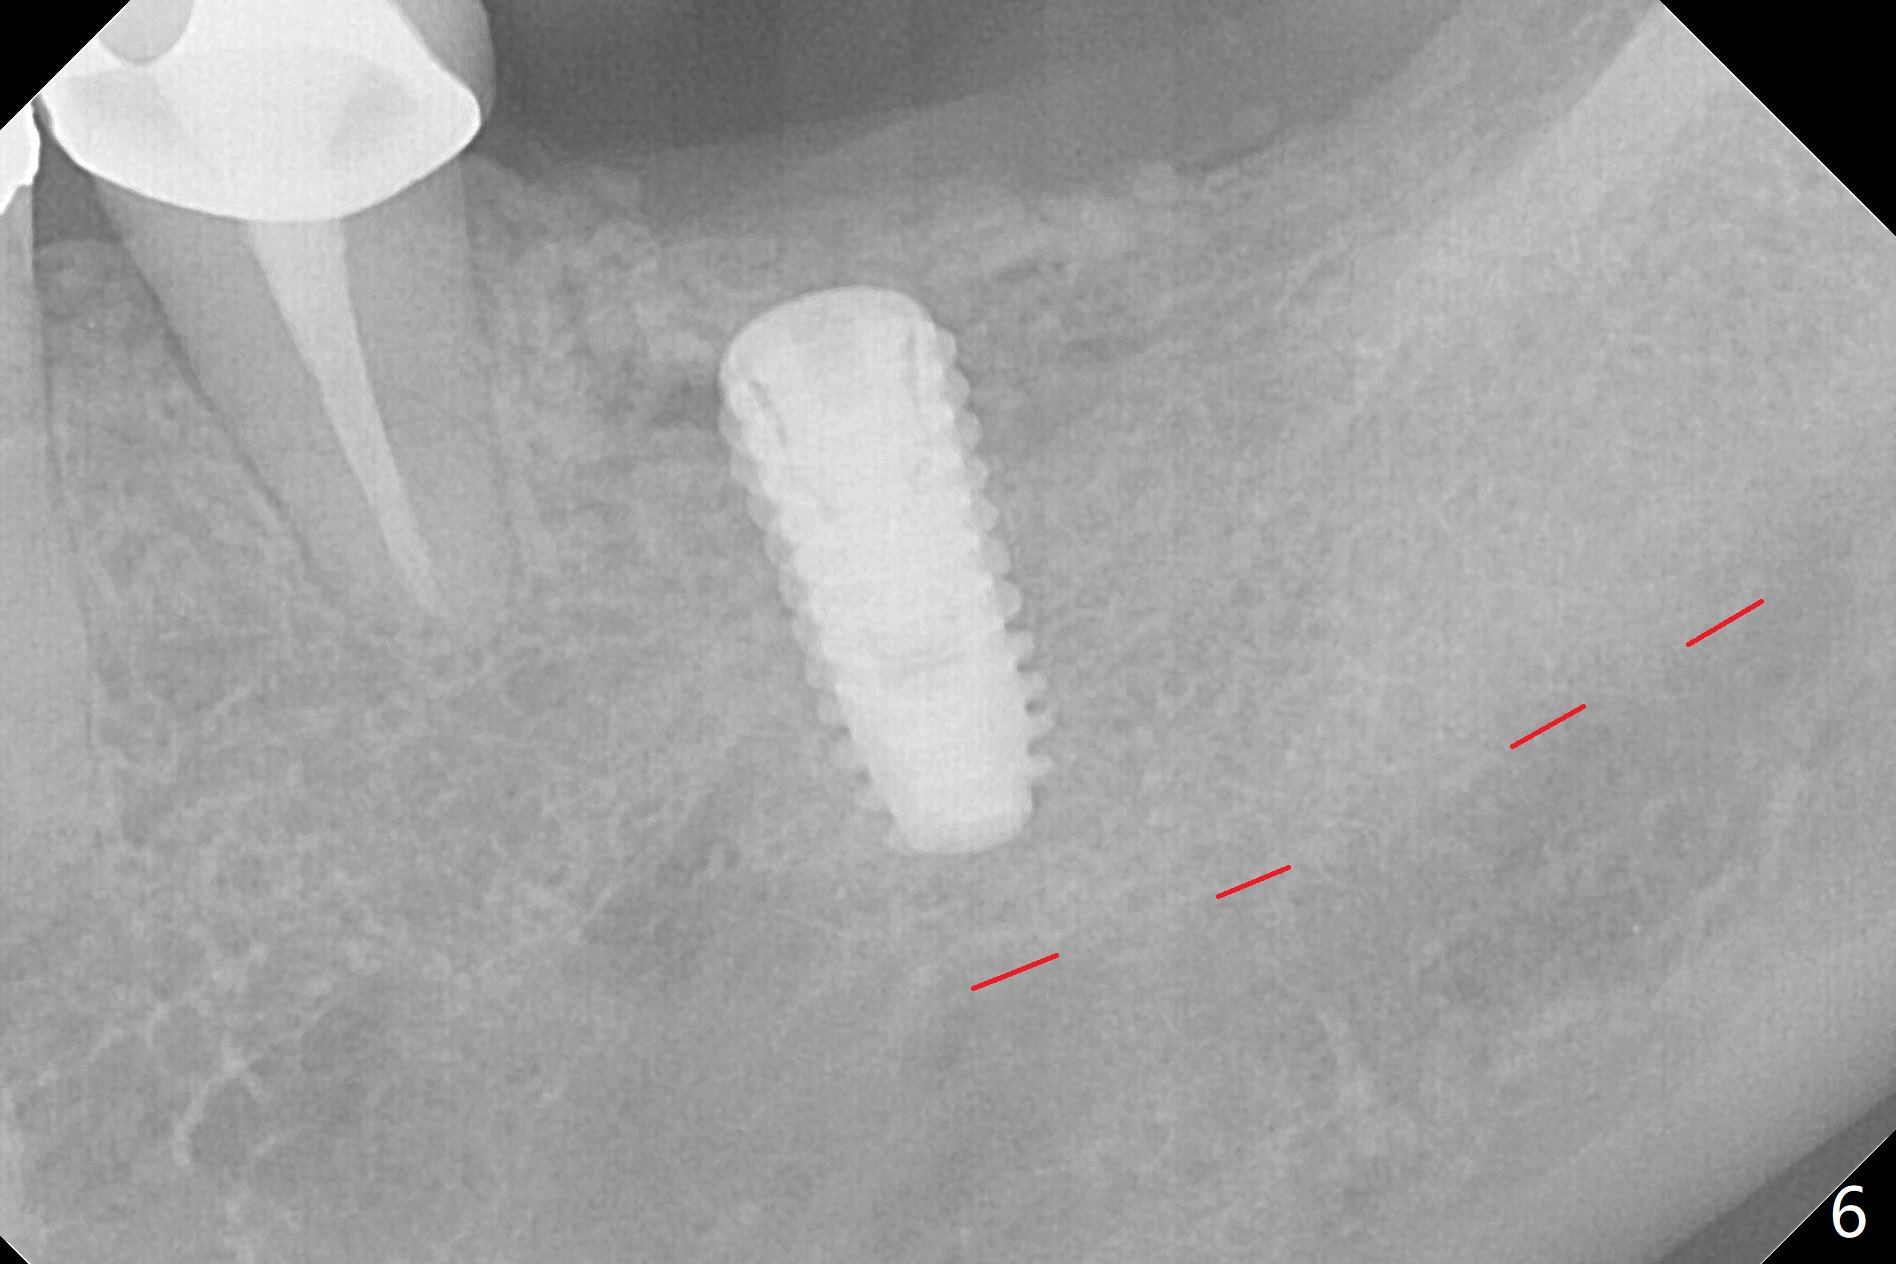

Allograft is placed around the fracture before suturing (Fig.5,6). To prevent potential buccal plate necrosis, the procedure should be terminated when the ridge is initially split (Fig.3) and restart in 3 weeks. Red dashed line: the superior border of the Inferior Alveolar Canal.